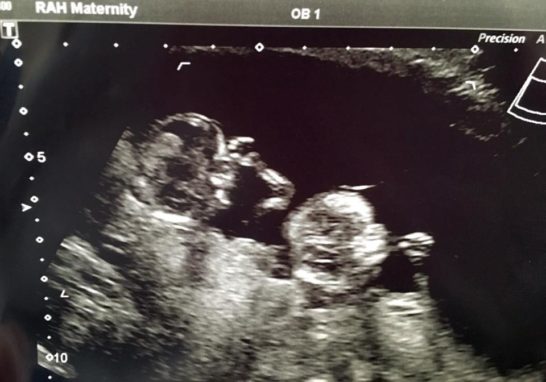

Claire and James Weir’s baby girls aren’t just a little special, they are miracle twins who defied all the odds.

Born premature and just a few days shy of the legal abortion limit at 24 weeks, Imogen and Annabelle are the youngest twins ever recorded in Great Britain. Weighing in at just about one pound each, the girls have been called “truly incredible” and “a miracle” for surviving.